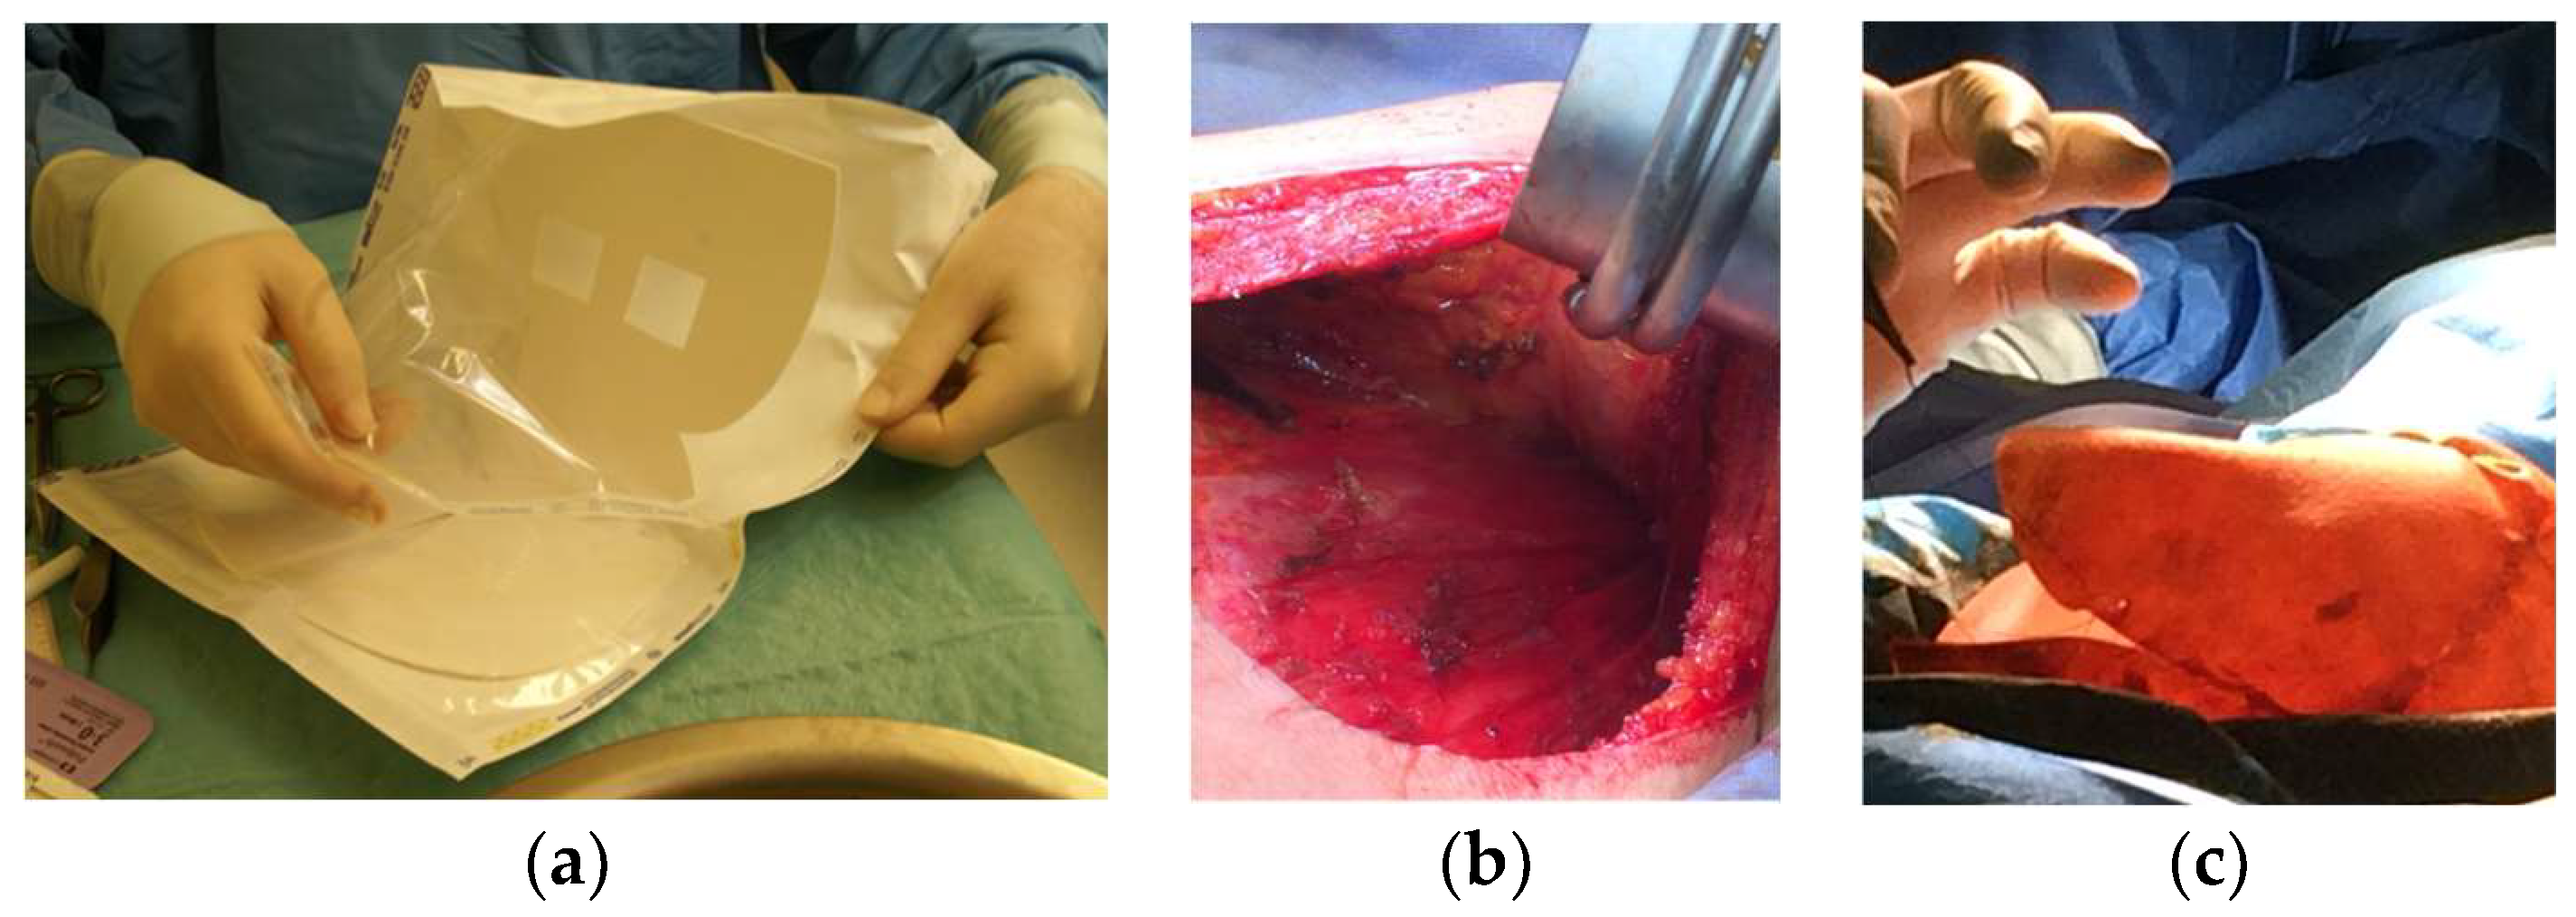

2.2.2. Acellular Dermal Matrices (ADMs)

2.3. Autologous Fat Reconstruction